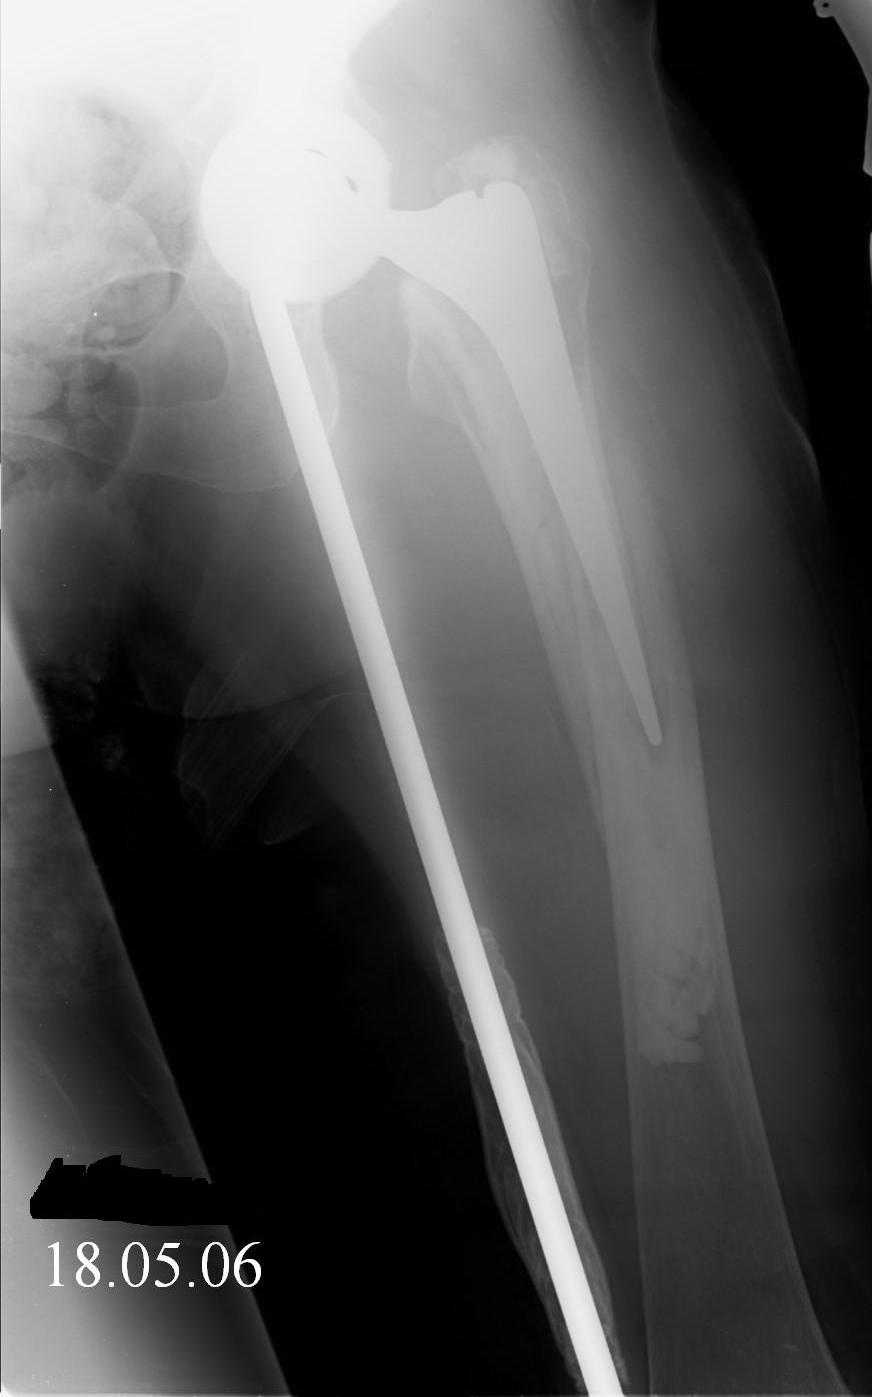

Hello! This is just illustration in one of the choice of treatment